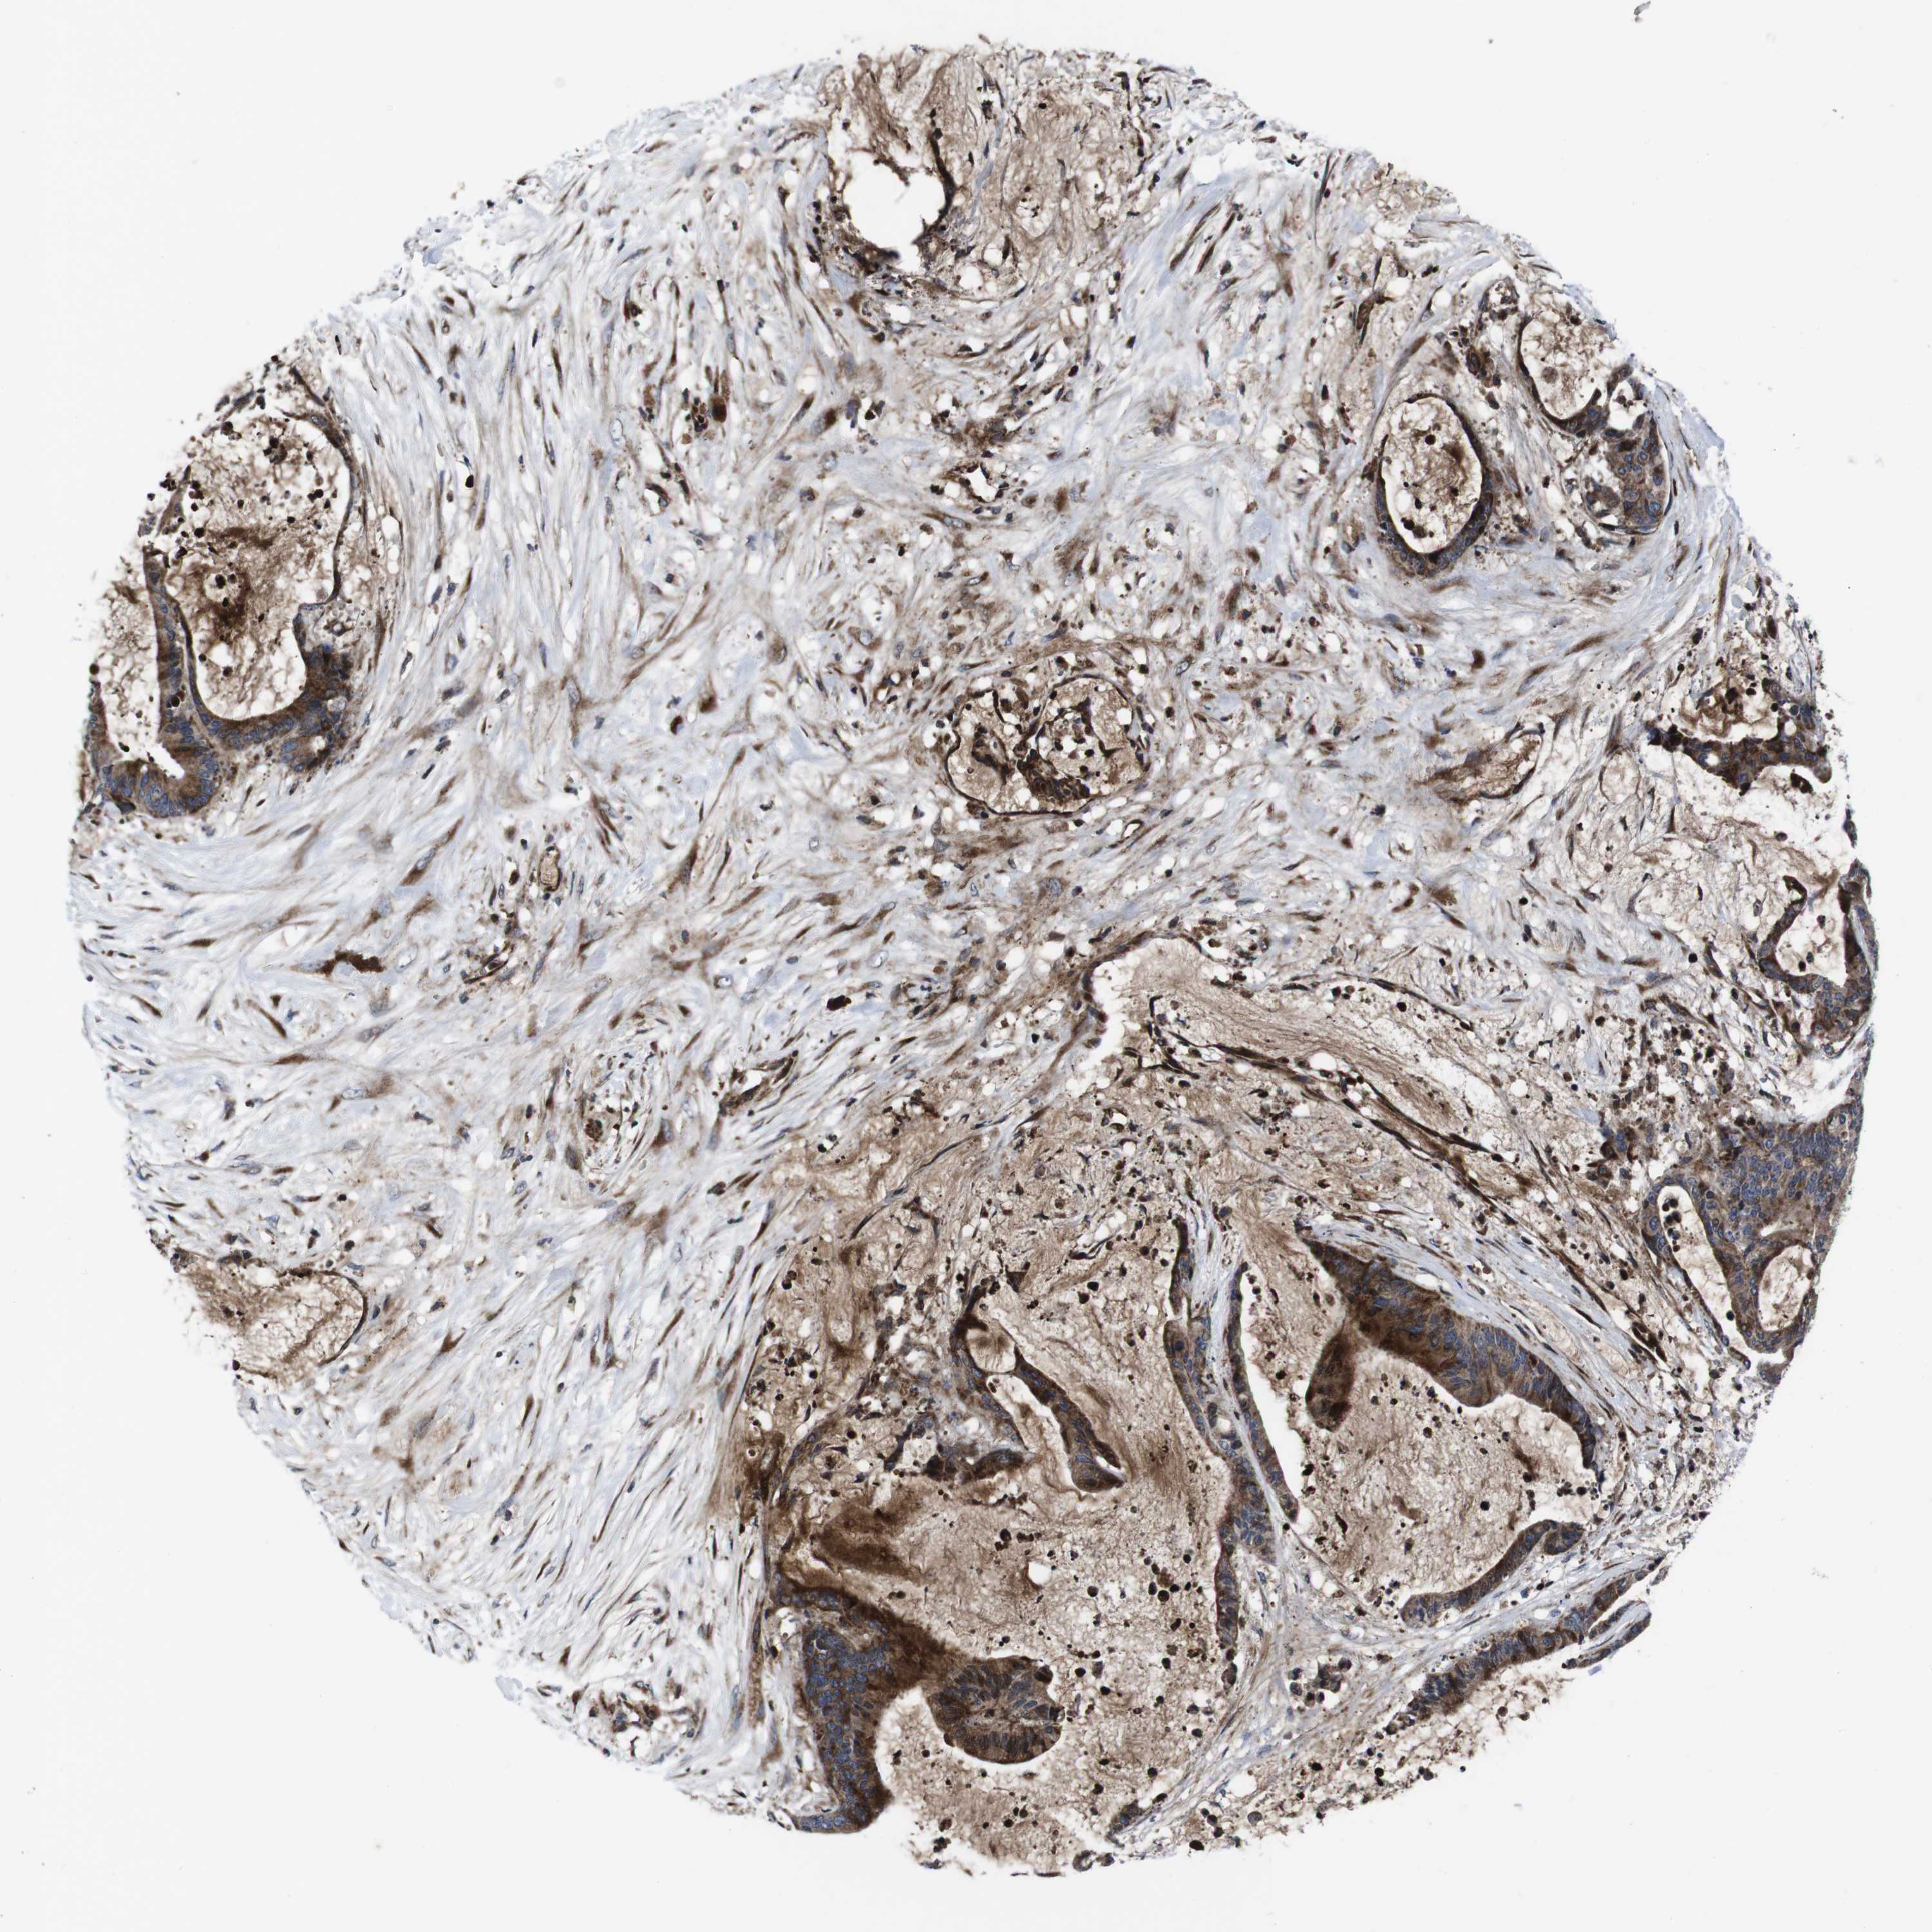

LIVER CANCER - Protein expressioni

A mouse-over function shows sample information and annotation data. Click on an image to view it in a full screen mode. Samples can be filtered based on level of antibody staining by selecting one or several of the following categories: high, medium, low and not detected. The assay and annotation is described here.

Note that samples used for immunohistochemistry by the Human Protein Atlas do not correspond to samples in the TCGA dataset.

Antibody stainingi

Antibody staining in the annotated cell types in the current human tissue is reported as not detected, low, medium, or high, based on conventional immunohistochemistry profiling in selected tissues. This score is based on the combination of the staining intensity and fraction of stained cells.

Each image is clickable and will lead to virtual microscopy that enables deeper exploration of all samples and also displays staining intensity scores, fraction scores and subcellular localization as well as patient and tissue information for each sample.

Antibody HPA045821

Antibody HPA054352

Antibody CAB012229

Staining

High

Medium

Low

Not detected

Intensity

Strong

Moderate

Weak

Negative

Quantity

>75%

75%-25%

<25%

None

Location

Nuclear

Cytoplasmic/membranous

Cytoplasmic/membranous,nuclear

Carcinoma, Hepatocellular, NOS

Cholangiocarcinoma